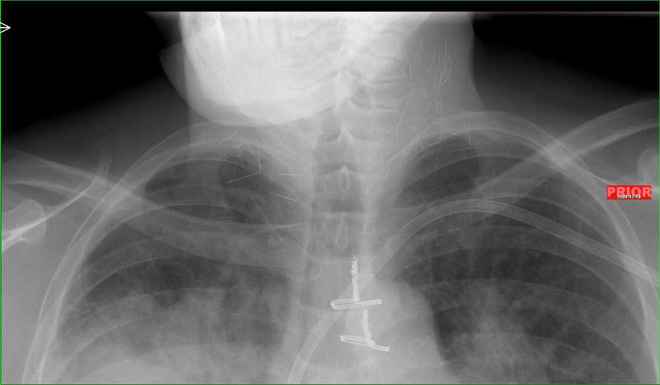

Mới đây một hình X-quang đã được chia sẽ lên mạng. Nhiều người nhìn bức hình đã phải giật mình. Trong cơ thể người nghiện có rất nhiều mũi kim.

Và mới đây, một bức hình chụp X-quang phần cổ của một con nghiện heroin lâu năm đang được chia sẻ với tốc độ chóng mặt. Quan trọng hơn, ai nhìn thấy nó cũng phải rùng mình.

Bạn có quan sát thấy những đường thẳng chi chít ở 2 bên cổ không? Bạn nghĩ đó là gì? Câu trả lời là những mũi kim tiêm.

Bức hình được một bác sĩ không rõ tên chia sẻ trên diễn đàn Reddit từ 4 năm trước, nhưng nay được cư dân mạng... đào mộ lại.

Theo đó, bệnh nhân là một con nghiện heroin lâu năm, đến bệnh viện trong tình trạng viêm phổi nặng. Nhưng đến khi đưa vào máy chụp X-quang, người ta phát hiện ra hàng tá mũi kim gãy vẫn còn trong cổ anh ta.

Theo thông tin từ vị bác sĩ, bệnh nhân này có vẻ như đã sử dụng heroin bằng cách tiêm chích. Khi tiêm vào cổ, thuốc lên quá nhanh khiến anh ta mất ý thức, buông tay và làm gãy kim tiêm.